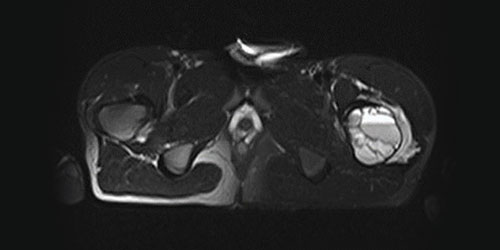

Clear cell sarcoma is a rare malignant soft tissue tumor. Unlike other soft tissue sarcomas, clear cell sarcoma often occurs in young patients and around the joints (knee, foot, and ankle).